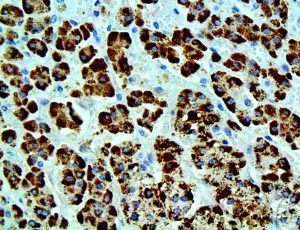

It is the ICU physician who is most likely to witness one of the deadliest manifestations of the abnormal immunological response, the cytokine storm syndrome (CSS). This response is also referred to by some as the cytokine release syndrome (CRS). CSS is characterized by continuous activation and expansion of macrophage and lymphocyte populations, which secrete large amounts of cytokines, causing the cytokine storm. This massive cytokine release is akin to hemophagocytic lymphohistiocytosis (HLH) disease, a syndrome characterized by initial unchecked and persistent activation of cytotoxic T lymphocytes and NK cells.

Clinical and laboratory manifestations of HLH include fever, enlarged liver and/or spleen, neurologic dysfunction, coagulopathy, liver dysfunction, cytopenias (i.e., low levels of erythrocytes, leukocytes, and/or platelets), hypertriglyceridemia, hyperferritinemia, hemophagocytosis, and eventually diminished NK cell activity as the immune system becomes progressively paralyzed. HLH can be familial (primary HLH) or secondary to another disease process (sHLH), such as rheumatic disease, in which it is referred to as macrophage activation syndrome (MAS, characterized by elevated ferritin).

This activation induces inflammatory monocytes to highly express IL-6, starting a localized and then systemic cascade effect that results in hyperproduction of IL-6, which accelerates the inflammatory process. Because IL-6 also increases vascular permeability, excessive levels cause blood vessels to become very leaky. This, along with clotting factors released from vascular endothelial cells, stimulates the coagulation cascade, resulting in microthrombosis (tiny clots), which leads to ischemia and tissue death of the kidney, intestines, heart, liver, brain and extremities.